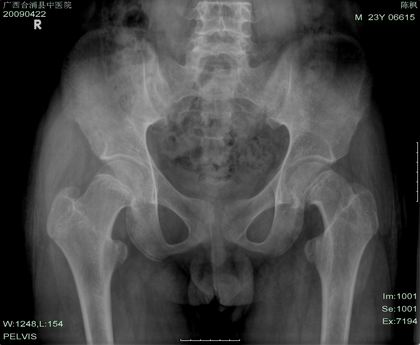

以下是引用杀毒软件在2009-4-22 19:28:00的发言:[br]长骨增粗见骨膜性成骨,多个骨骺线未闭,骨质疏松,左胫骨内卵圆形透亮区,边缘硬化。[br][br]结合临床符合----垂体内分沁骨病。可惜现有资料诊断并不具特征性。 [br][br]加照---蝶鞍和颅盖看看[br][br]胫骨内卵圆形透亮区---考虑---纤维性骨皮质缺损可能性大,不完全排除----低毒感染

以下是引用hhx58在2009-4-22 18:50:00的发言:[br]男,23岁。有脑垂体瘤手术病史。[br]

以下是引用余辉在2009-4-22 20:41:00的发言:[br]患者23岁,骨骺未闭合,有垂体瘤手术史,提示垂体前叶功能低下,生长激素分泌低下,骨龄延迟.[br]所示各骨密度减低,下部腰椎侧弯,双侧股骨颈弯曲,且似有looser带,股骨头二次骨化中心内似有囊状影重叠,左侧胫骨髁间嵴及胫骨上干骺端见囊性改变.胫骨干皮质有分层,提示骨质软化,纤维囊性骨炎及骨膜功能异常等.[br]此为患者垂体整体功能低下(前后叶均功能低),对内分泌调节作用就低下,会使各种内分泌激素均产生紊乱,所以本例内分泌改变是混合性的,骨骼改变由多种内分泌异常引起,至少符合甲旁减\\甲旁亢\\肾上腺皮质功能亢进\\雄激素分泌异常等改变[br][br][本贴已被 余辉 于 2009-4-22 20:43:08 修改过]